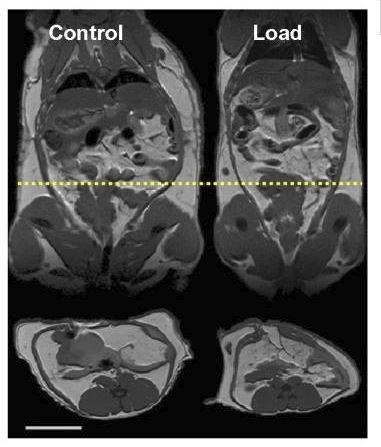

Hay un estudio muy interesante donde se les implantaron cápsulas con “mini pesas” en el abdomen a roedores obesos (muy parecido a hacer rucking)12.

Los roedores comenzaron a perder peso de forma espontánea después de esta intervención:

Al final del experimento, el peso total (peso biológico + peso de los implantes) fue similar entre los 2 grupos:

Además, el grupo con la carga extra (“Load” en la imagen de abajo) llegó a perder más grasa corporal que el grupo de control (seguían pesando más por las mini pesas, pero su peso biológico llegó a ser menor):

Qué es el rucking imagen 4

Los investigadores del estudio analizaron muchos datos, incluido el cuánta actividad física tenían los roedores, la cual fue muy parecida en ambos grupos.

Esto nos muestra que la pérdida de peso no se debió a que tuvieron mayor actividad.